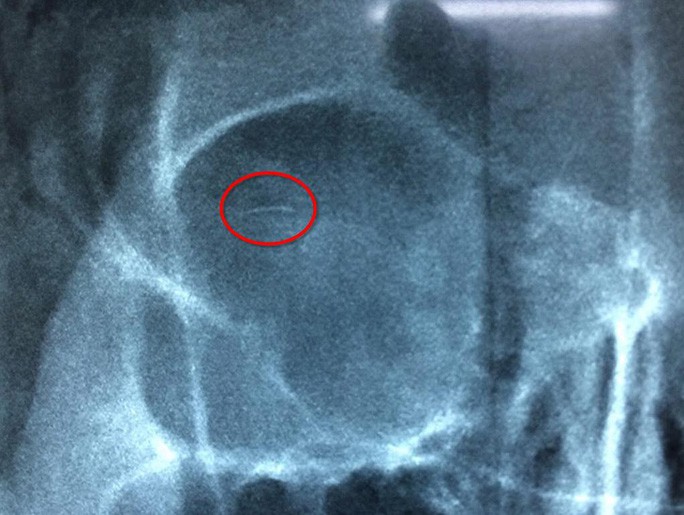

Kết quả phim chụp X-quang cho thấy trong mắt cô gái có hình ảnh lờ mờ một cây kim dài khoảng 5 mm, đường kính 0,2 mm to bằng sợi lông mi. Dị vật nằm ở 1/3 trên ngoài hốc mắt, song song với cùng đồ kết mạc. Các bác sĩ tại BV Mắt Trung ương đã phẫu thuật ngay cho bệnh nhân nhưng không tìm được cây kim. Phải đến lần thứ hai phẫu thuật, bác sĩ mới mò tìm được dị vật.

Dị vật nằm ở 1/3 trên ngoài hốc mắt, song song với cùng đồ kết mạc.